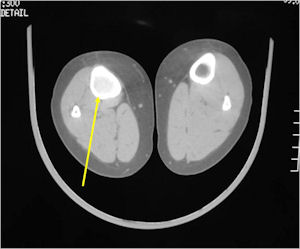

Plain X-Rays:

- Lucent nidus surrounded by a zone of marked sclerosis

- The nidus may demonstrate mineralization/ossification usually from the center outward that appears as a central zone of density within the nidus

- A nidus that is heavily ossified may blend in with the surrounding sclerosis and be difficult to detect on a plain x-ray.

- Periosteal bone is solid, rarely lamellated

- Cortical and subperiosteal osteoid osteomas are usually associated with much more reactive sclerosis than medullary tumors

- The periosteal reaction is continuous and often appears as cortical thickening (benign appearing reaction)

- Intracapsular osteoid osteomas are difficult to identify because there is no periosteum in the intracapsular region and hence a periosteal reaction does not occur.